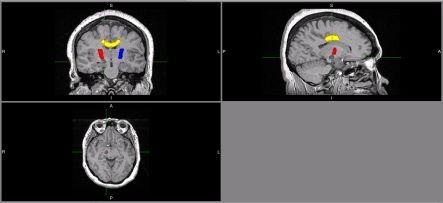

These images are of an MRI brain scan of someone who recently experienced a stroke. The stroke is the small dark area, under the green crosshairs. The top left image is looking at the person from the front; top right is looking at them from the side; lower left is looking up at them from their feet. The area coloured yellow is the corpus callosum, a thick bundle of connections between the two sides of the brain. The areas coloured red and blue are the posterior limbs of the internal capsules. These contain connections that carry movement commands from the surface of the brain to the spinal cord. Notice that the stroke affects the border of the red internal capsule, and this resulted in severe arm and leg weakness on the opposite side of the body. (Images courtesy of the Centre for Brain Research at the University of Auckland)